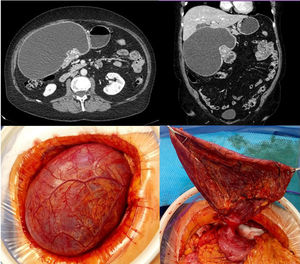

The patient is a 67-year-old woman under study for postprandial fullness and weight loss. Computed tomography (CT) scan revealed a mass in the gastric antrum measuring 18 × 10 cm that was compatible with a duplication cyst. In surgery, we performed controlled evacuation of the content and subsequent division of the pedicle with an endoscopic stapler. The pathological result was spindle cell proliferation with fibromyxoid stroma, compatible with plexiform fibromyxoma. This is a rare benign mesenchymal neoplasm that has only recently been described in an antral location. These lesions are typical of middle-aged adults, presenting very heterogeneous symptoms, and their differential diagnosis should include other myxoid lesions of the gastric wall (Fig. 1).